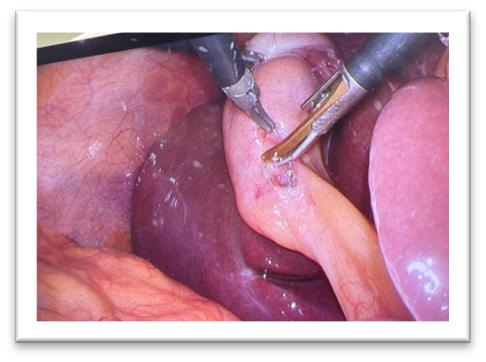

香川(医科)大学を卒業して29年目になり、これまで急性期病院にて消化器外科を中心に診療してまいりました。胃・食道の外科を専門とし、腹腔鏡手術を含む消化器外科全般と内視鏡診療も行っております。